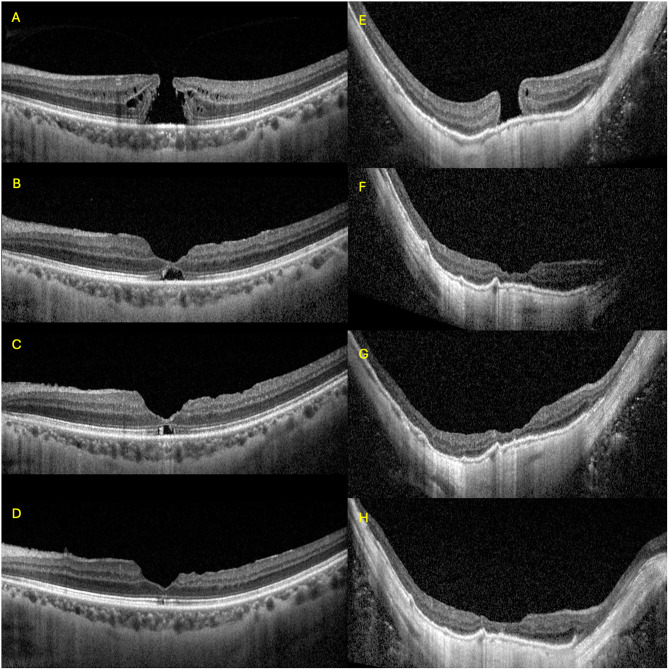

Patient and methods: This is a retrospective case-control study of patients who underwent MH repair between 2018 and 2022. HM was defined by axial length (AL) ≥26 mm. MH size, macular curvature and foveoschisis were graded. Surgical technique was divided into internal limiting membrane (ILM) peel or flap. Post-operative best corrected visual acuity (BCVA) and anatomical outcomes including hole closure, restoration of outer retinal layers, presence of foveal gliosis or foveal detachment were assessed at post-operative one, three, six and twelve months.

Results: Thirty-four HM eyes were matched 1:1 to 34 out of 201 non-HM eyes with using gender, age, MH size and concurrent phacoemulsification as covariates. Mean AL in the HM group was 28.46 ± 2.01 mm, ranging from 26.03 to 32.83 mm. MH size was 366±183 µm and 386±199 µm in HM and non-HM groups (p=0.667). BCVA and restoration of outer retinal layers were comparable between groups at all time points. Initial hole closure rate was comparable, with 29 (85.3%) in HM group vs 30 (88.2%) in non-HM eyes, p=0.720. One eye in the HM group re-opened 10 months post-operatively. Proportion of eyes with non-closure was higher in those who underwent ILM peel vs flap [7/34 (20.5%) vs 0/34 (0%), p=0.022]. Smaller MH was associated with better closure rate (OR 0.99, 95% CI 0.99-1.00). AL and macular curvature were not associated with hole closure (OR 0.91, 95% CI 0.72-1.15; OR 1.01, 95% CI 0.99-1.02 respectively). Larger MH was associated with poorer final BCVA (β=0.010, 95% CI 0.007-0.014).

Conclusion: Anatomical success was comparable between HM and non-HM eyes. Higher surgical success was associated with smaller MH size and ILM flap, but not influenced by AL, macular curvature or foveoschisis.